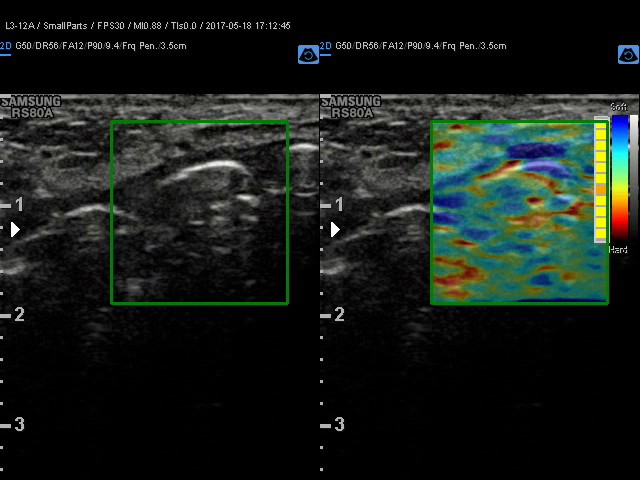

Elastografia.

To przełomowa metoda diagnostyczna wykorzystującą fakt, że chora tkanka zmienia swoją twardość. Można powiedzieć, że elastografia jest cyfrowym rozwinięciem badania dotykiem, kiedy lekarz ocenia twardość i spoistość badanego narządu.

Elastografię proponujemy przede wszystkim w przypadkach:

• podejrzanych zmian w tarczycy

• podejrzanych zmian w piersiach

W wielu przypadkach elastografia pozwala uniknąć biopsji i rozwiać wątpliwości co do łagodnego, lub złośliwego charakteru zmiany.

Badanie elastograficzne można wykonać w naszej pracowni jako rozszerzenie badania USG tarczycy i piersi (ocena guzków), a także jako samodzielne badanie – elastografia wątroby w celu oceny włóknienia(stosowana u nas metoda elastrografii 2D-SWE jest znacznie dokładniejsza od dotychczas stosowanej metody TE [FIBROSCAN®].